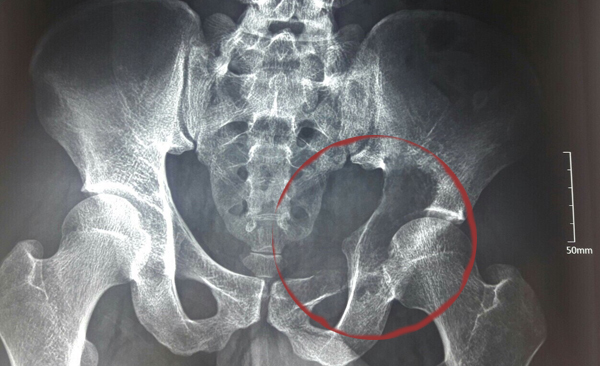

| Khối u kích cỡ lớn phá huỷ ổ cối và xâm lấn cả vào ổ bụng |

Sau khám, các bác sĩ BV K định có một khối u ở vùng ổ cối xương chậu, phá huỷ hoàn toàn ổ cối và phát triển vào ổ bụng bệnh nhân với kích cỡ khoảng 10cm, là u tế bào khổng lồ.

Các bác sĩ đánh giá, đây là ca bệnh hết sức phức tạp, vị trí khối u là nơi tập trung dây thần kinh ngồi cùng với các bó mạch thần kinh mông trên và mông dưới đi qua, là khu vực hiểm yếu, có nguy cơ tai biến trong phẫu thuật rất cao.

Ngoài ra, vùng đáy ổ cối bị phá huỷ khiến khớp háng bệnh nhân mất chức năng gần như hoàn toàn.